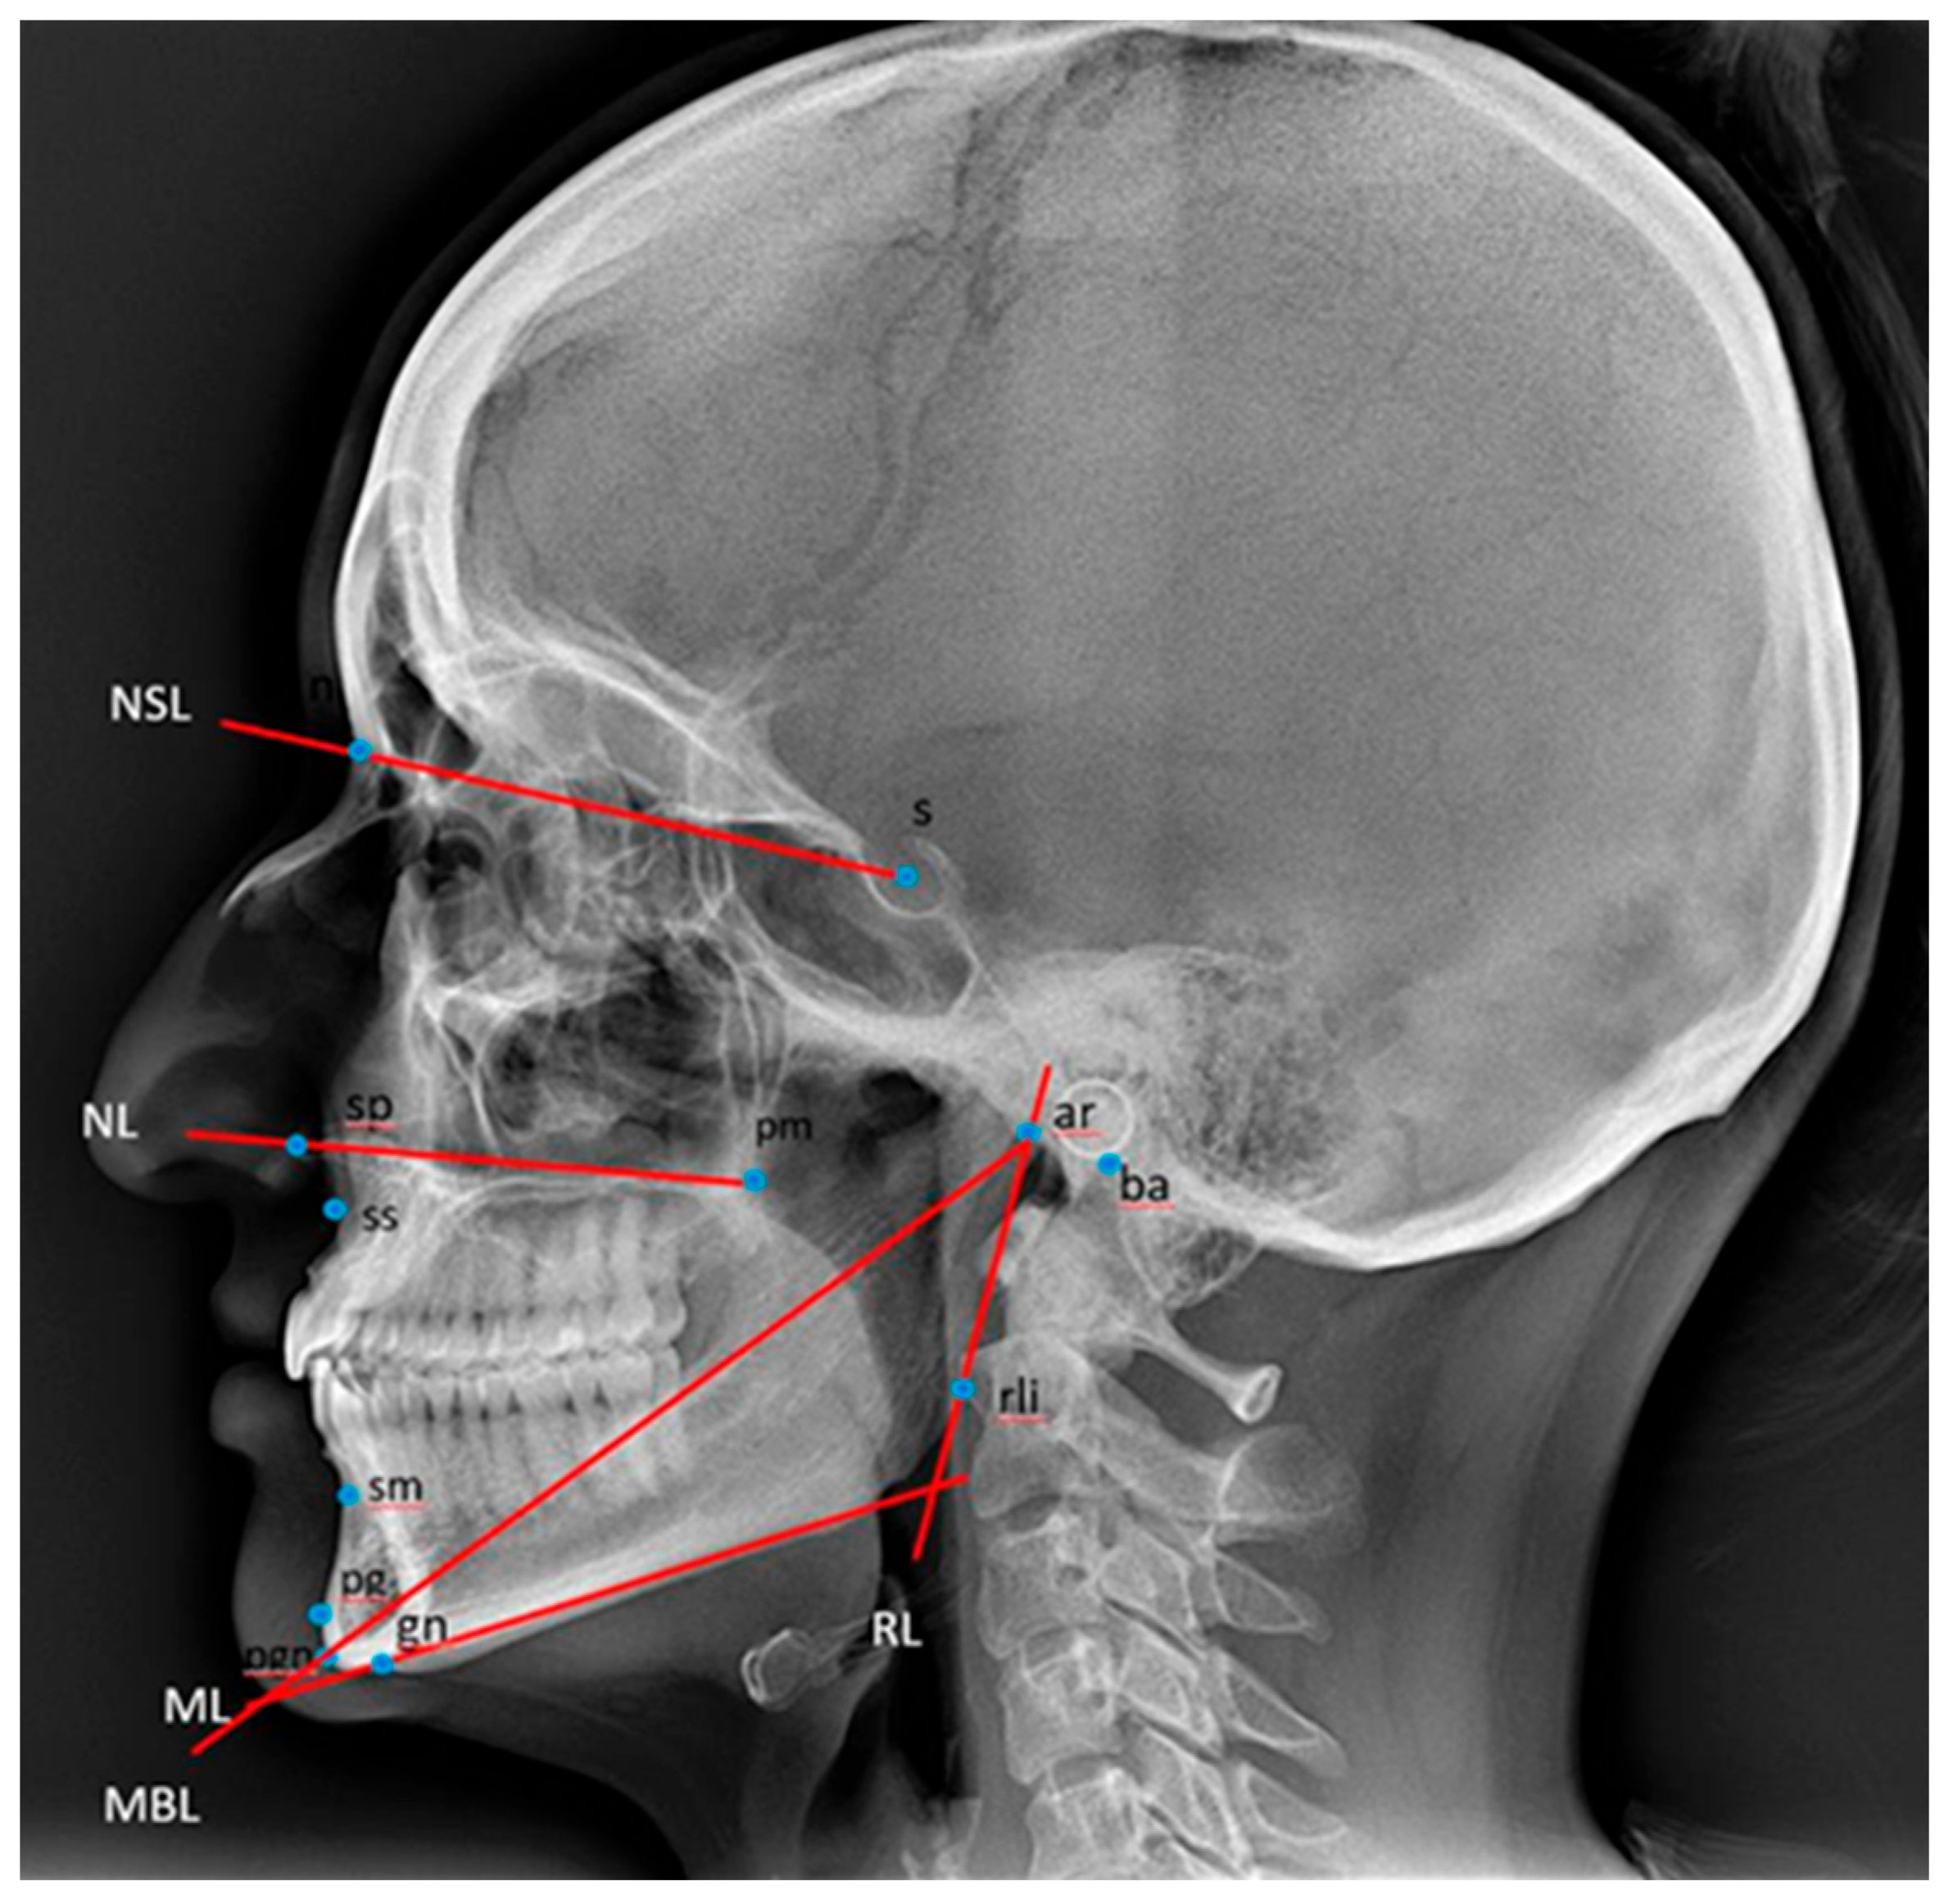

2.2.1. Cephalometric Analysis of Lateral Cephalograms

- Christensen, H.C.; Melsen, B. Roentgencephalometry, 2nd ed.; Department of Orthodontics, The Dental School: Aarhus, Denmark, 2004. [Google Scholar]

| ML/RL | 51 | 103.8 | 132.2 | 117.76 | 6.01 | 74 | 105.4 | 134.2 | 118.16 | 6.31 | 0.045 *cd |

| MBL/ML | 51 | 15.7 | 32.3 | 22.5 | 3.22 | 74 | 15.7 | 28.4 | 21.09 | 2.42 | 0.006 **b |

| s-n-ss | 51 | 76.1 | 92.7 | 82.58 | 3.72 | 74 | 75.8 | 92.6 | 83.76 | 3.57 | 0.020 * |

| s-n-pg | 51 | 68.9 | 89.5 | 80.67 | 4.44 | 74 | 75 | 93.7 | 82.36 | 3.89 | 0.032 *a |

| s-n-sm | 51 | 69.1 | 86.2 | 79.24 | 4.10 | 74 | 74.2 | 91.5 | 81.12 | 3.86 | 0.009 *a |

| ss-n-pg | 51 | −7.8 | 10.5 | 1.75 | 3.31 | 74 | −6.1 | 7.7 | 1.23 | 2.98 | 0.761 |

| ss-n-sm | 51 | −3.2 | 9.5 | 3.35 | 2.52 | 74 | −4 | 9.1 | 2.62 | 2.41 | 0.450 |

| Vertical variables | |||||||||||

| NSL/NL | 51 | −0.4 | 12.9 | 5.61 | 3.19 | 74 | −4.6 | 13.2 | 5.95 | 4.09 | 0.792 |

| NSL/ML | 51 | 11 | 42 | 27.35 | 6.99 | 74 | 15 | 41.7 | 27.95 | 5.61 | 0.677 |

| NL/ML | 51 | 7.6 | 33.3 | 21.74 | 5.29 | 74 | 11.9 | 33.3 | 21.89 | 5.06 | 0.496 |

| NSL/OLf | 51 | −5.2 | 26.6 | 12.93 | 6.3 | 74 | −0.4 | 73.7 | 13.9 | 8.8 | 0.426 |